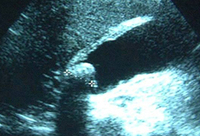

Foto operatória mostrando colecistite aguda

Do acervo do Dr Charles Bellows; usado com permissão